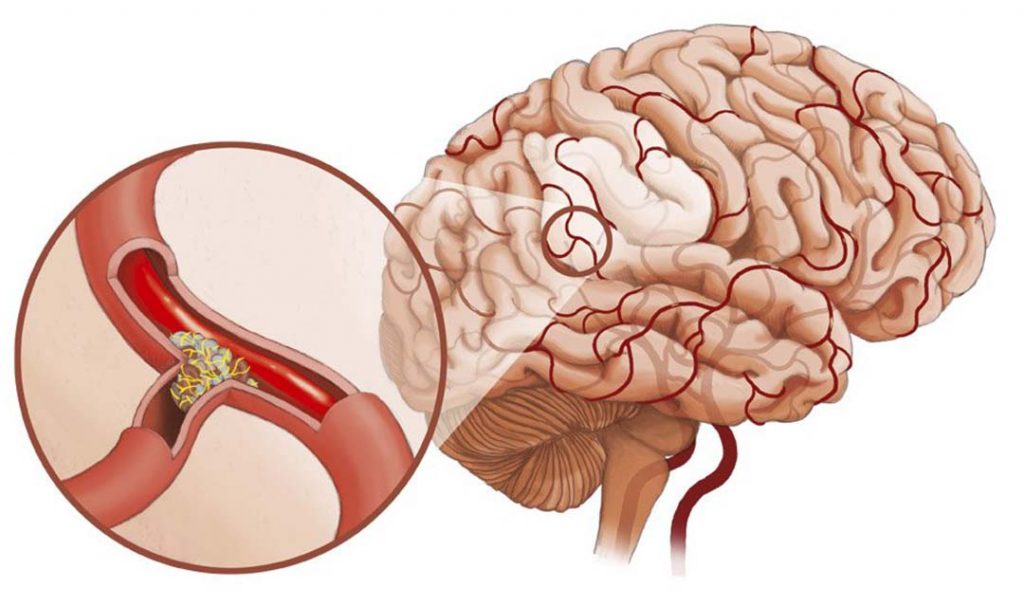

Хроническая ишемия головного мозга и лейкоареоз: симптомы и лечение